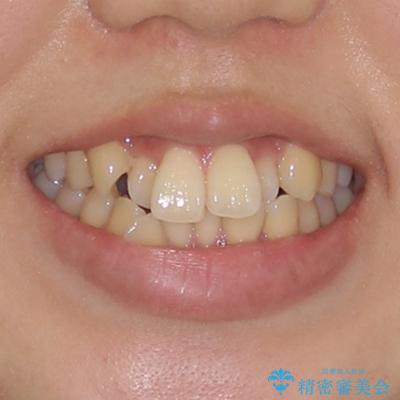

- 前歯のデコボコやクロスバイトと上顎の前突感による口の閉じにくさを気にして来院された患者様です。

目立たない装置を希望されたので、上顎が裏側装置のハーフリンガルを選択し、上下左右の小臼歯(計4歯)を抜歯して矯正治療を行うこととしました。

表側のワイヤー矯正に比べると治療期間は長く、費用も高額となりますが、どうしても目立たせたくないという方にはお勧めの抜歯矯正です。